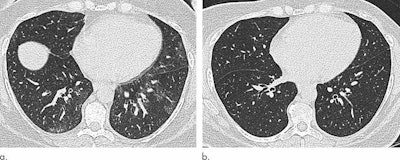

Copley also referred to a study she and a team conducted last year that was published in Radiology that used CT to assess lung parenchymal and tracheal morphology before and six months after patients underwent bariatric surgery. This investigation showed that particular imaging abnormalities improved after patients lost weight.

Mosaic attenuation | 33.3% | 13.7% |

End-expiratory air trapping | 92.2% | 29.4% |

Tracheal area | 201 mm2 | 229 mm2 |

"CT extent of air trapping correlates most with decreased lung capacity in obese people, [and improvement in] air trapping was the main determinant for decreased dyspnea following surgery," she said.

Bariatric surgery and weight loss appear to reverse some of the negative effects of obesity on the respiratory system, Copley noted. CT has great potential to improve understanding of obesity's impact on the respiratory system, but there have been few CT studies evaluating obesity's effects on the lungs and the trachea.

Her team has observed differences on chest CT images obtained in obese individuals, causing the researchers to wonder if these differences were due to obesity and whether they were reversible after weight loss.